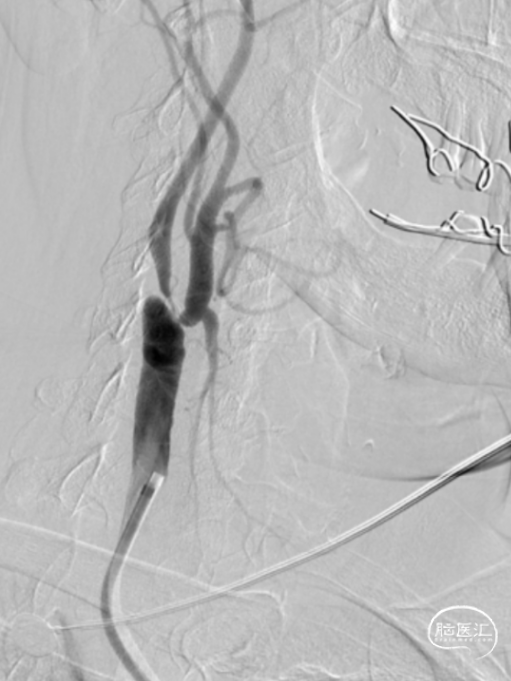

术前评估:术前MRA提示右侧颈动脉起始部重度狭窄大于90%。患者颈总动脉直径9.07mm,颈内动脉直径4.11mm,颈总颈内直径相差较大。

造影提示右侧颈内动脉起始段狭窄,狭窄率约95%,右侧大脑前显影浅淡,前交通开放。左侧颈内动脉通过前交通向右侧大脑前动脉代偿供血。后交通开放,向右侧大脑中动脉代偿供血。

1

术中置入0.014mm微导丝通过颈外动脉狭窄,应用2*20mm球囊预扩张狭病变处后置入直径5mm保护伞至右侧颈内动脉C1段远端。